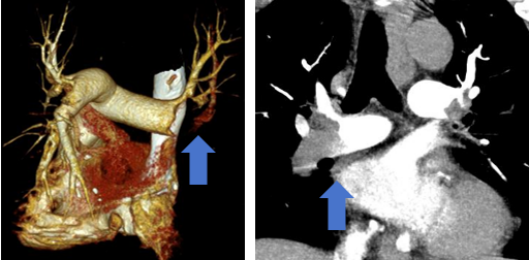

肺动脉CTA显示右侧肺动脉大面积肺动脉栓塞(箭头所指)